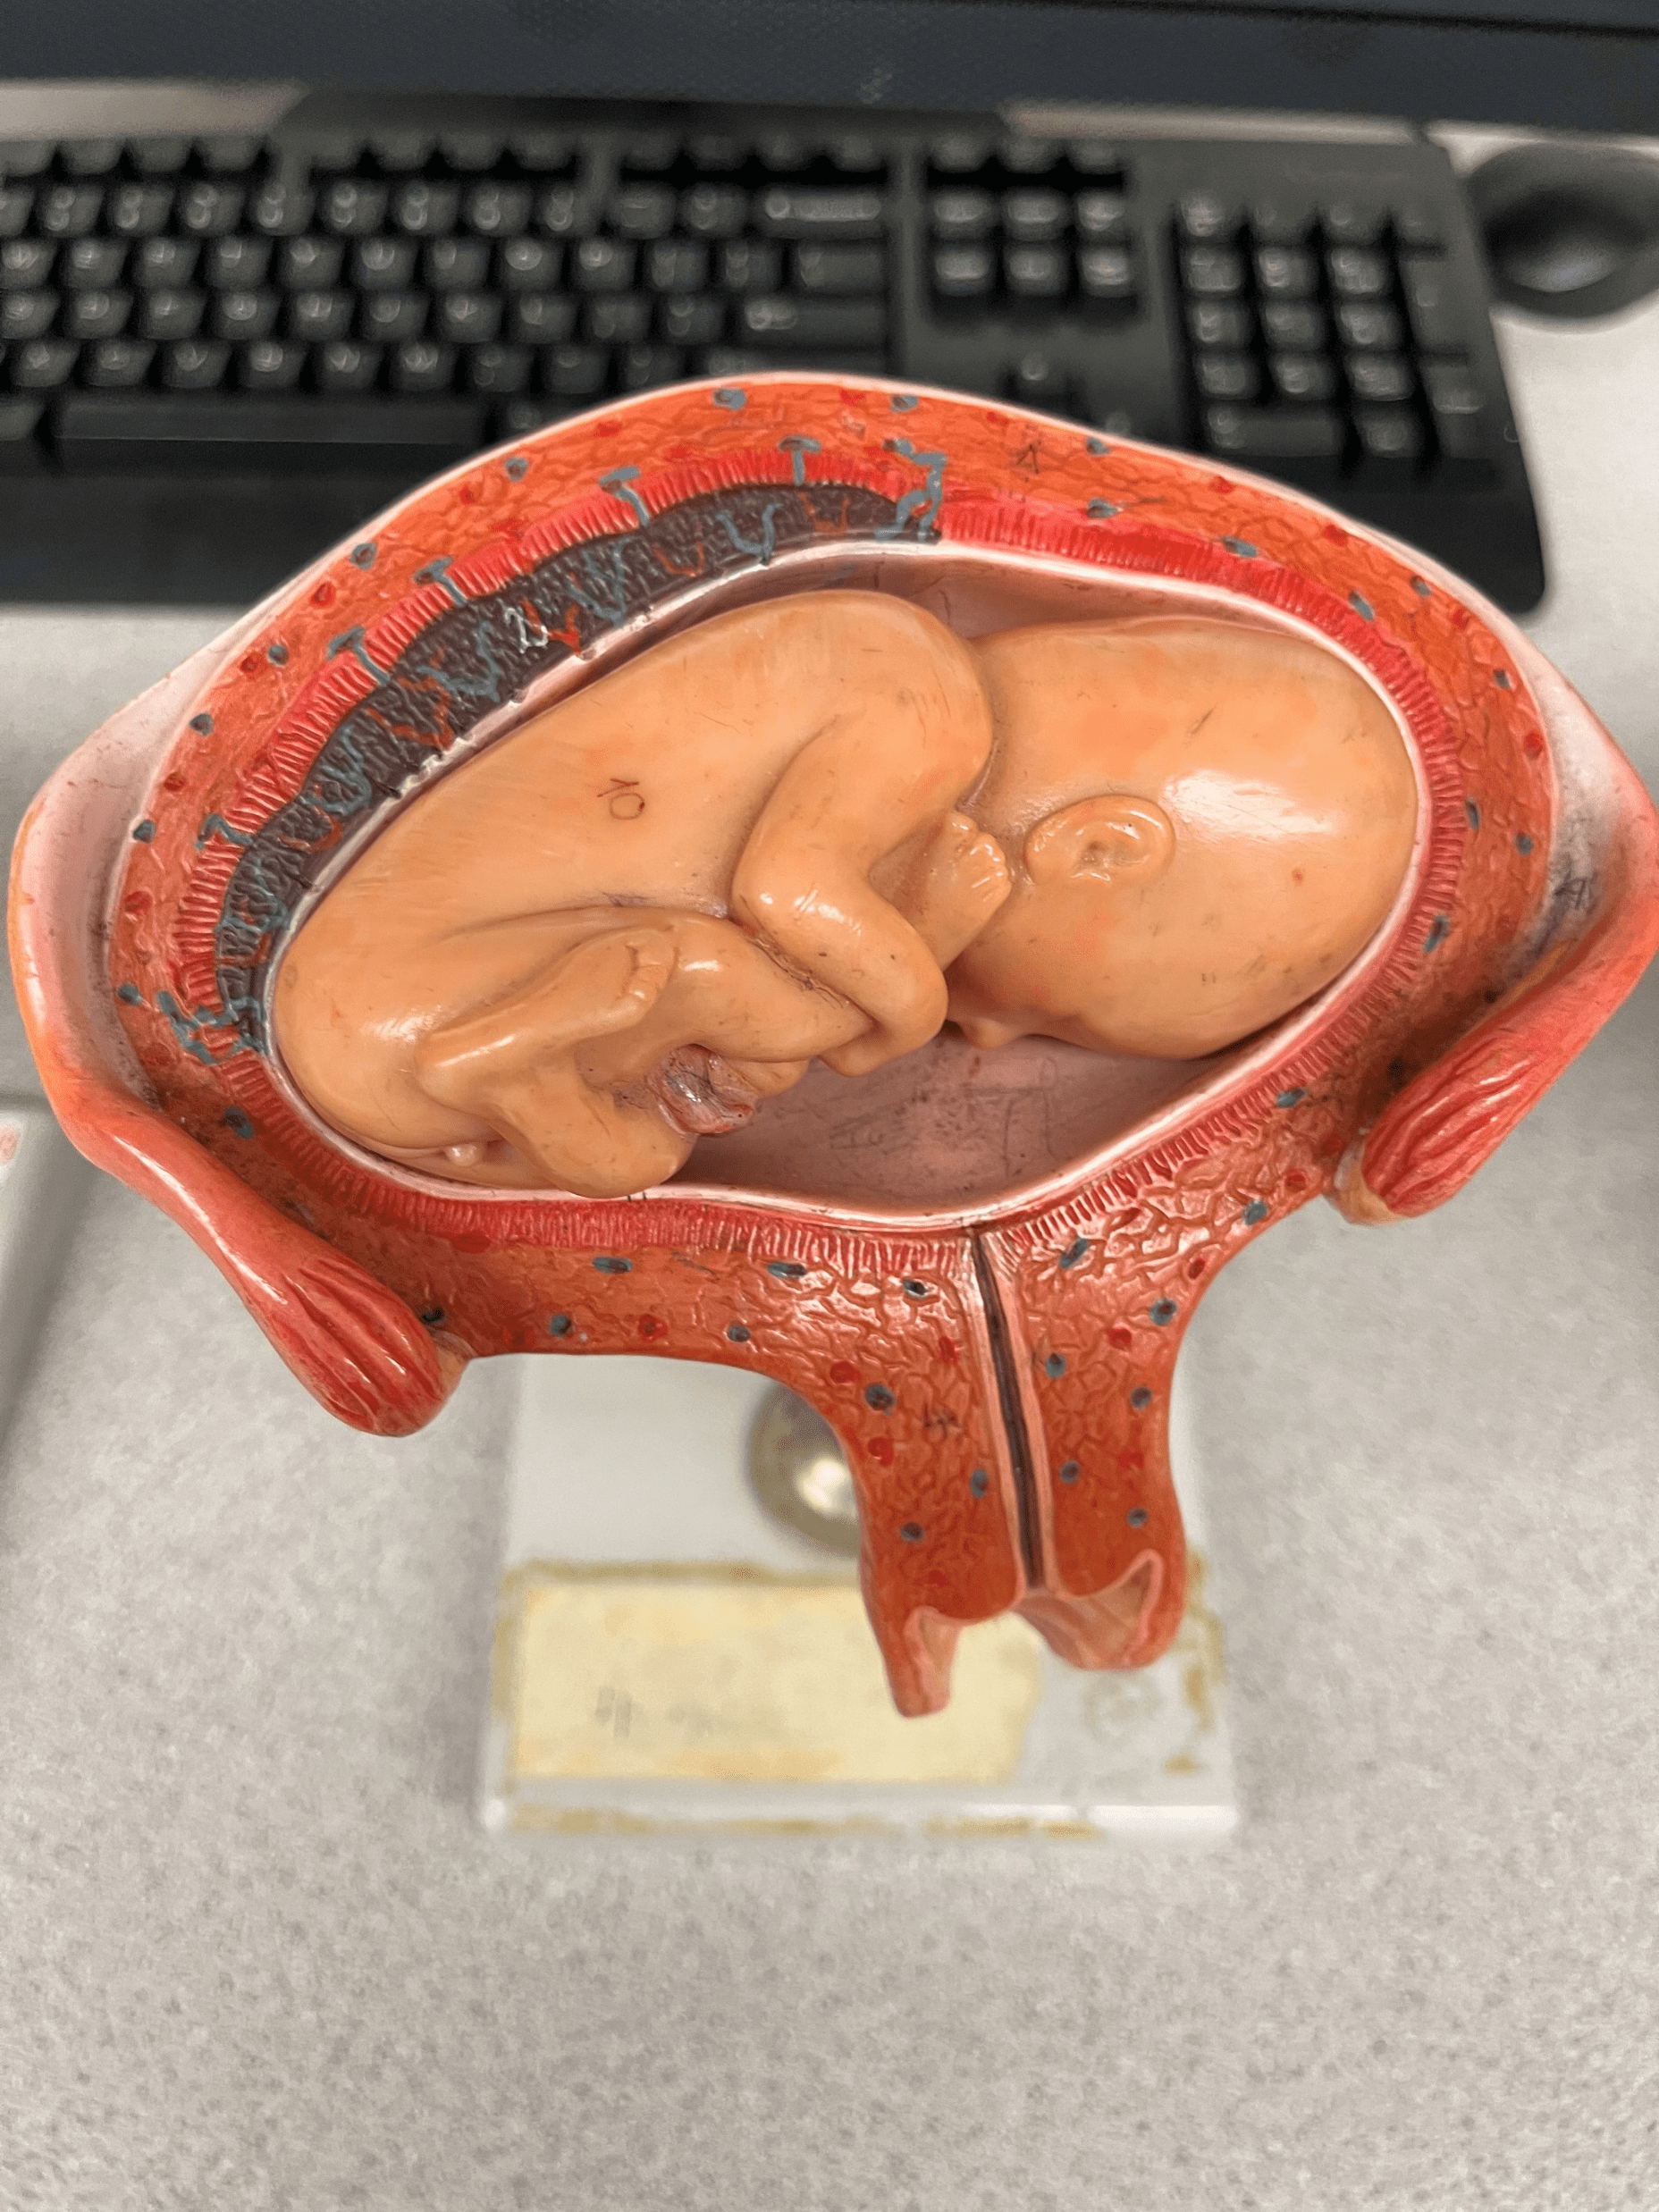

prone position

• Model of the developing fetus in the uterus.

• The position in which the fetus faces downwards.

• The position in which the fetus faces downwards.

16

New cards

breech position

• Model of the developing fetus in the uterus.

• The position in which the feet face downwards.

• The position in which the feet face downwards.

17

New cards

dorsal position

• Model of the developing fetus in the uterus.

• The position in which the fetus faces upwards.

• Also known as the supine position.

• The position in which the fetus faces upwards.

• Also known as the supine position.

18

New cards

normal position

• Model of the developing fetus in the uterus.

• The position in which the head faces downwards.

• Also known as the vertex position.

• The position in which the head faces downwards.

• Also known as the vertex position.

19